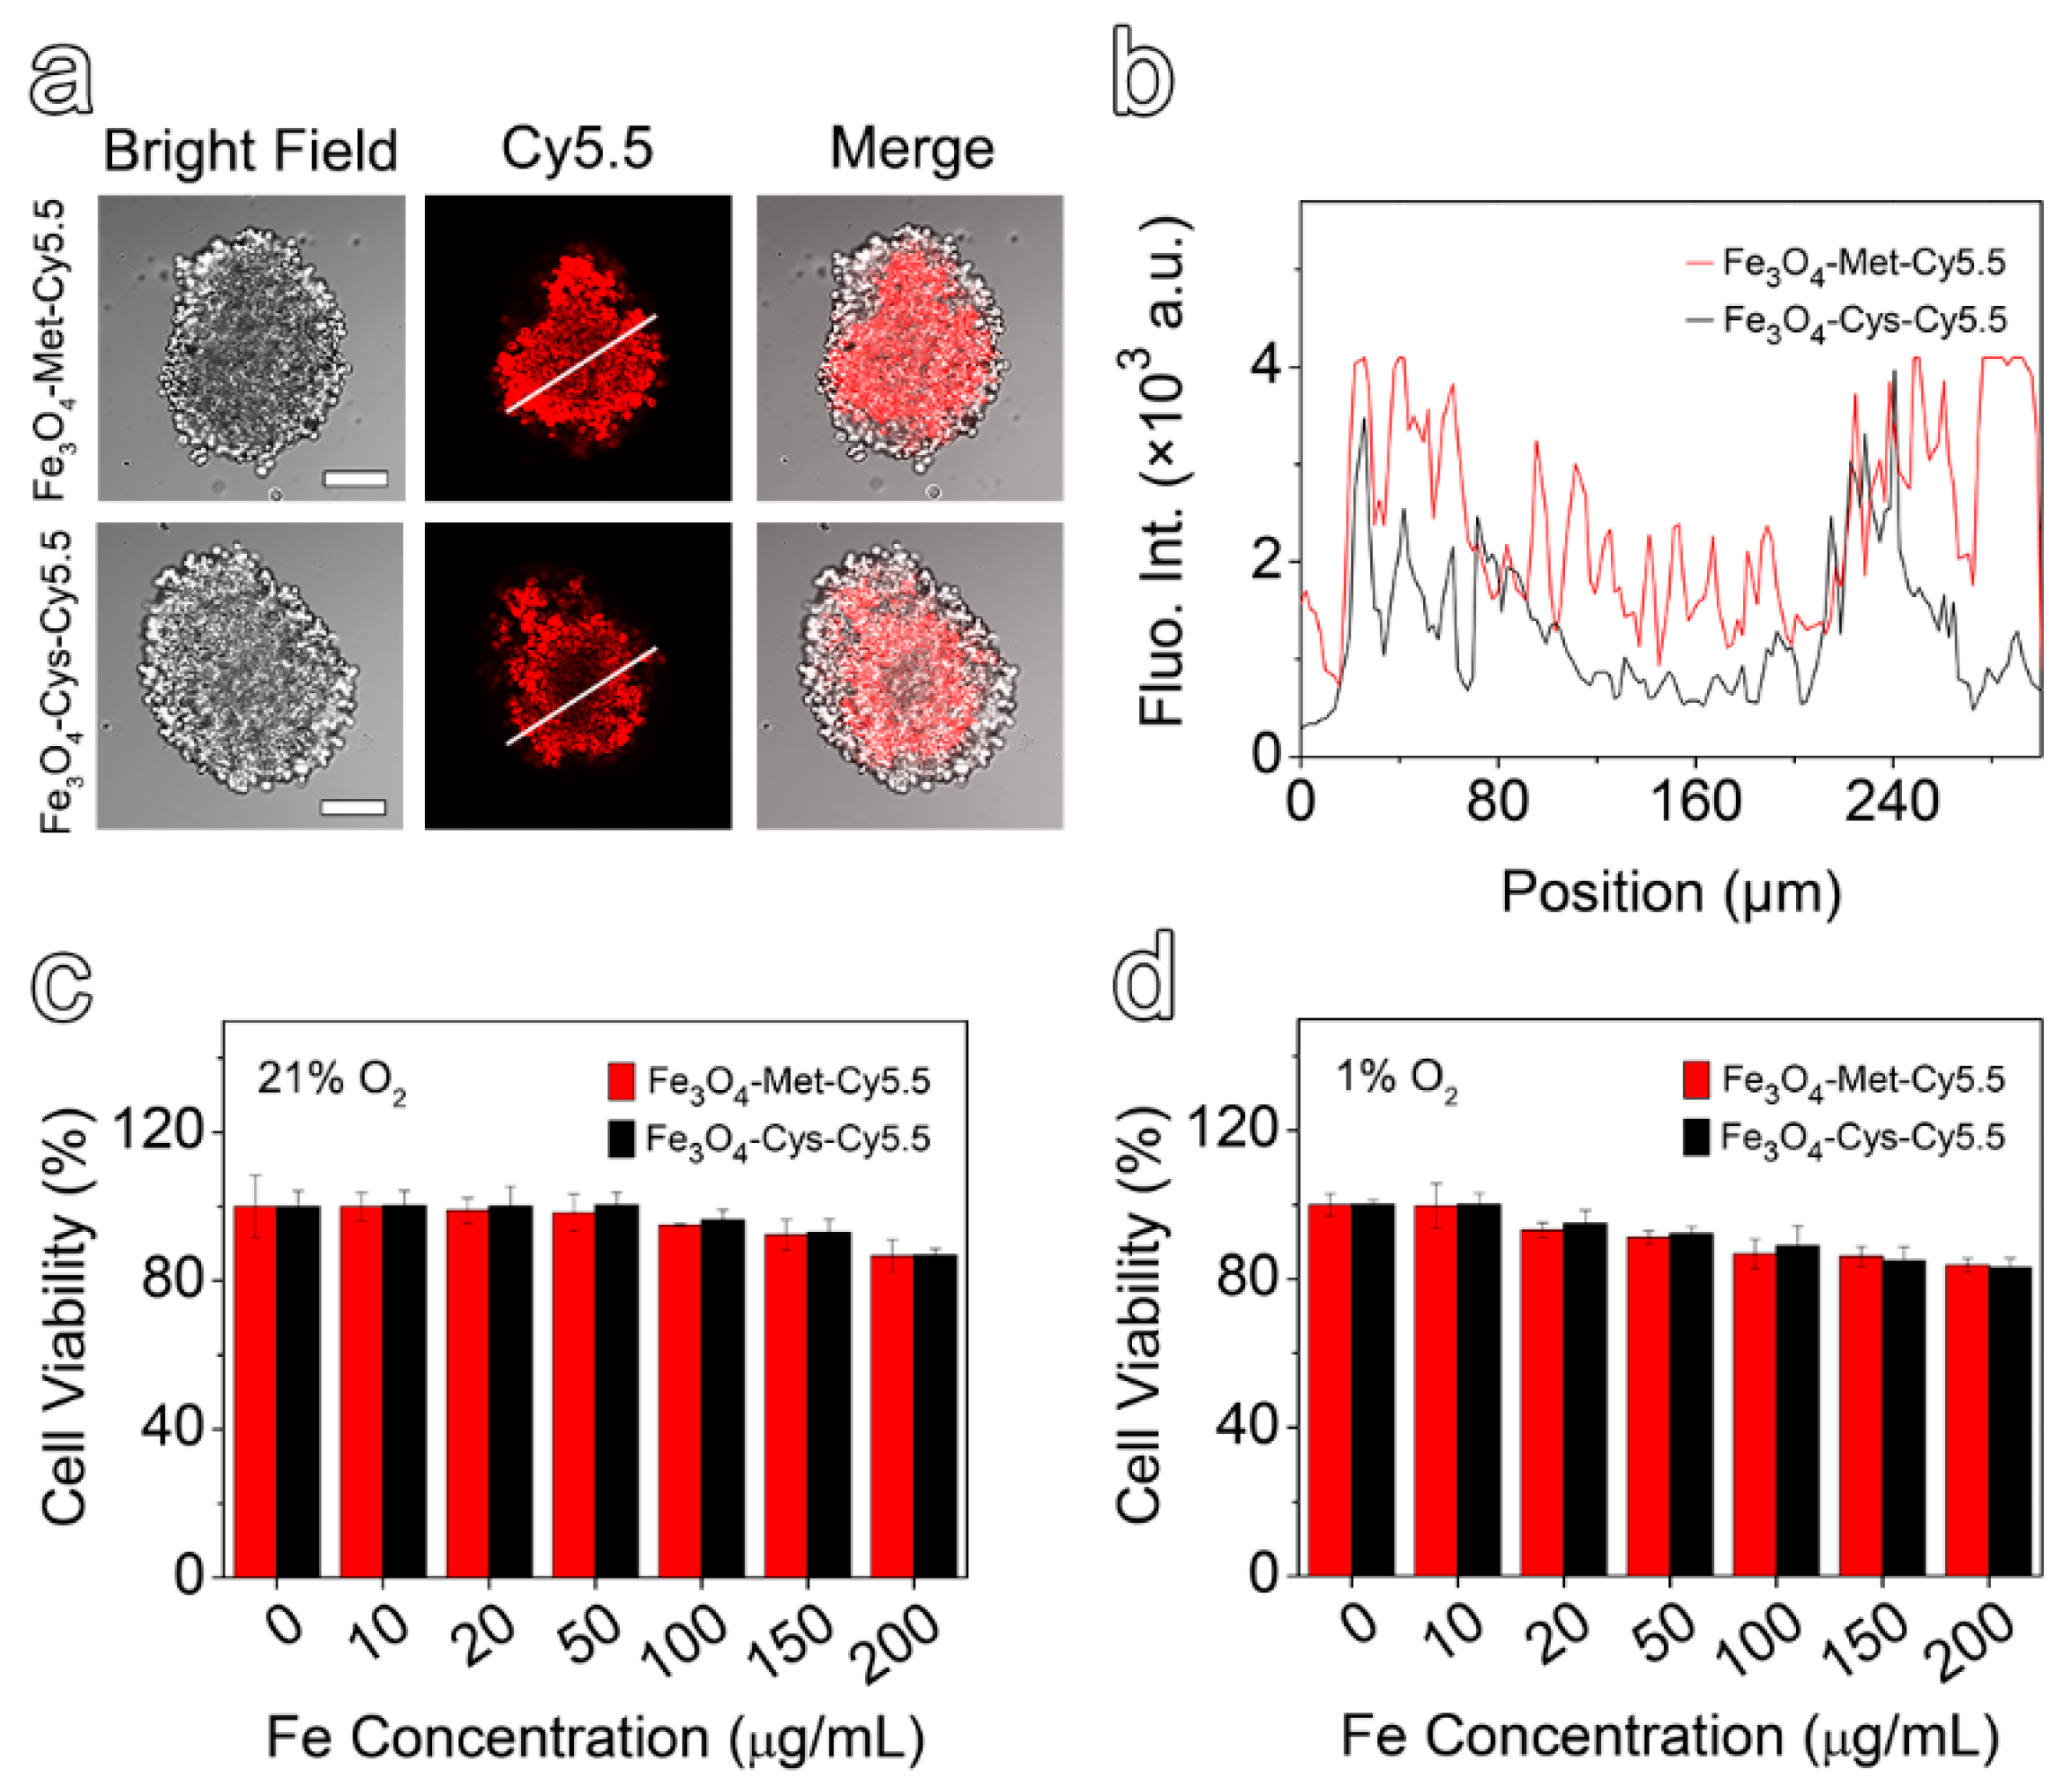

3.3. In Vitro Specificity and Cytotoxicity of Hypoxia-Sensitive MRI Nanoprobes